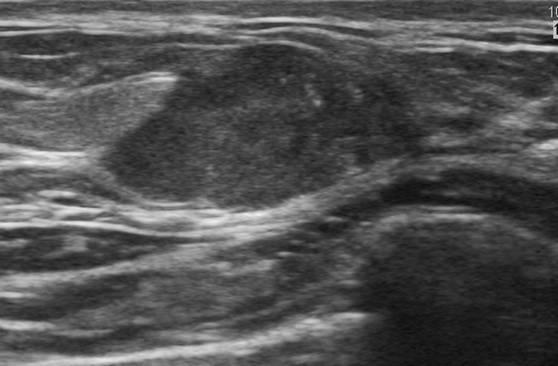

Ung thư vú

» Thông tin: Nữ giới – 33 tuổi.

» Lâm sàng: Khối tuyến vú.